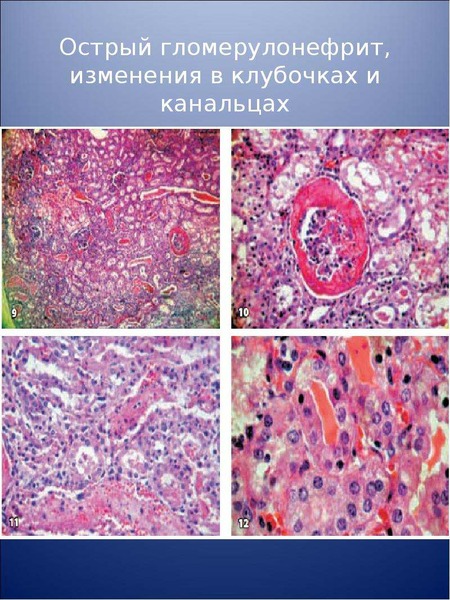

Механизм остро го диффузного гломерулонефрита